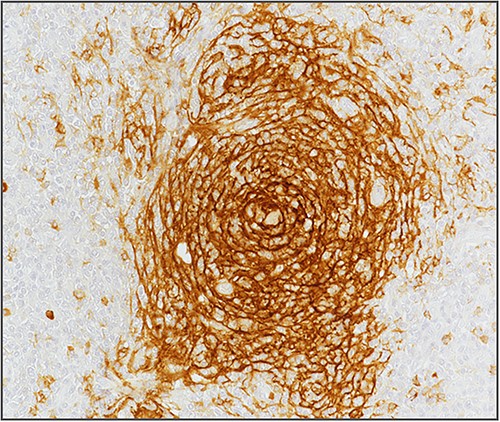

Blood investigations including hematological and biochemical tests revealed a low lymphocytes count with a consequent increased neutrophils percentage, and an increased protein C reactive (PCR) value. Oncological markers were normal. He was also tested for HIV infection, HHV-8, and Epstein–Barr virus with negative results. Positron emission tomography (PET) was performed with evidence of increased metabolic activity at the site of the mass. A suspicious diagnosis of Schwannoma or liposarcoma was made. The patient underwent CT-guided percutaneous biopsy with extemporary histological diagnosis of hyaline-vascular variant Castleman disease. The patient was subdue to laparoscopic removal of the mass. The mass was located near the duodenum without other structures involvement, from which it was isolated and entirely resected comprehending the intact capsule. No intra- and post-operative complications were recorded. The microscopic examination revealed the presence of a single lymph node measuring 7 × 5 × 4.5 cm with clear margins and an architecture characterized by the presence of small follicles distributed over the entire surface, lacking clear centers and polarization (primary follicle or atrophic follicle type), some with prominent vascularization and fibrosis (hyaline-vascular transformation), hyperplasia of the CD21+ follicular dendritic cells (Figs 3 and 4), and a “target” arrangement of the mantle lymphocytes. Large follicles with hyperplastic germinative centers and follicles with small centers duplicate germinatives, marked paracortical interfollicular vascular hyperplasia, and poor polytypic interfollicular plasmacytosis with very low proportion of IgG4+ plasma cells, coexist (Fig. 5).

Minimum amount of IgG4-secreting plasma cells (staining with anti-IgG4 antibody) (arrows).